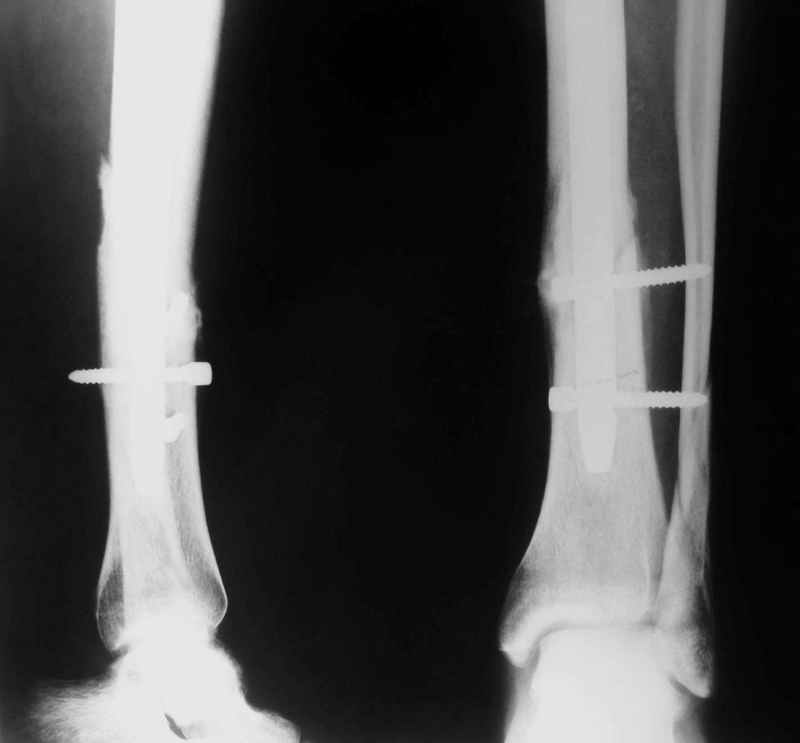

Перелом спиральный, то есть низкоэнергетический, так что со сращением дело обстоит уже неплохо, лишь бы "костоеда" не развилась. Отломки выглядят уже стабилизированными костной мозолью, так что довводить винты, наверно, уже незачем. Разве что при клинической оценке подвижность еще есть - тогда можно для стабилизации наложить простейший аппарат, не опасаясь контакта его элементов с гвоздем, поскольку места в дистальном метафизе оставлено более чем достаточно.

С Александром согласен, нет необходимости делать дополнительные усилия для сращения, не большая компрессия аппаратом из двух колец и полная нагрузка доделает работу.